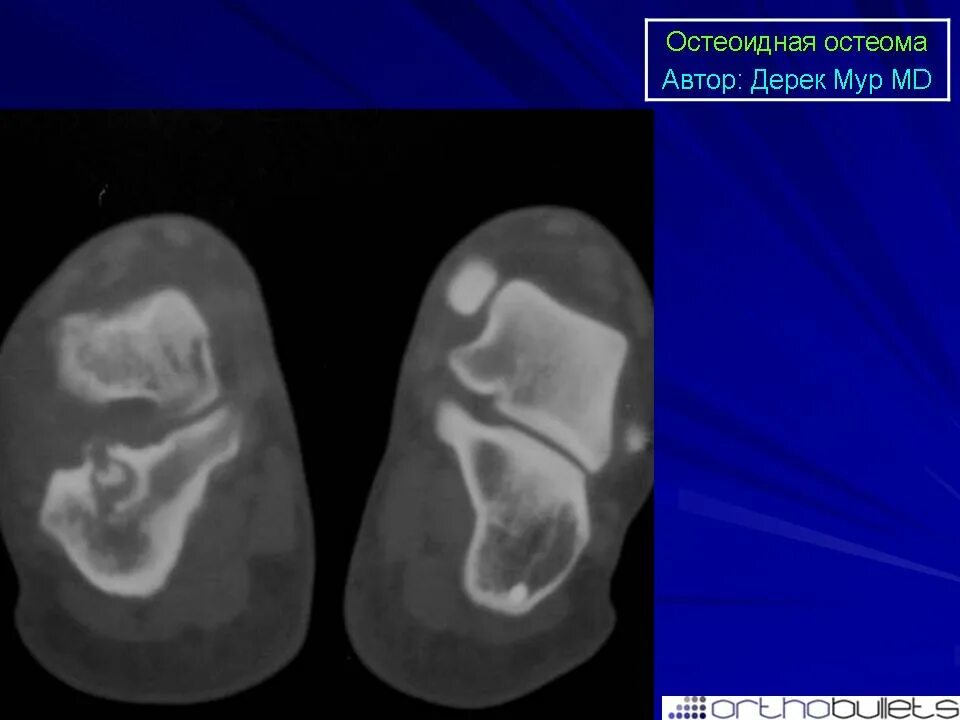

Остеома мрт